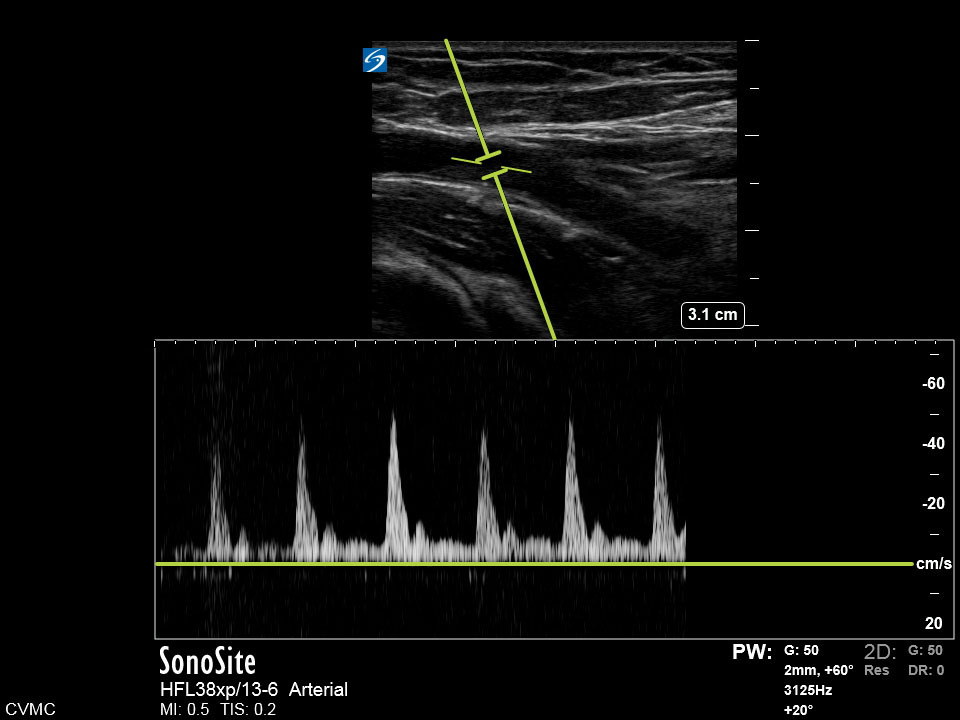

Dialysis AV Graft PW Image